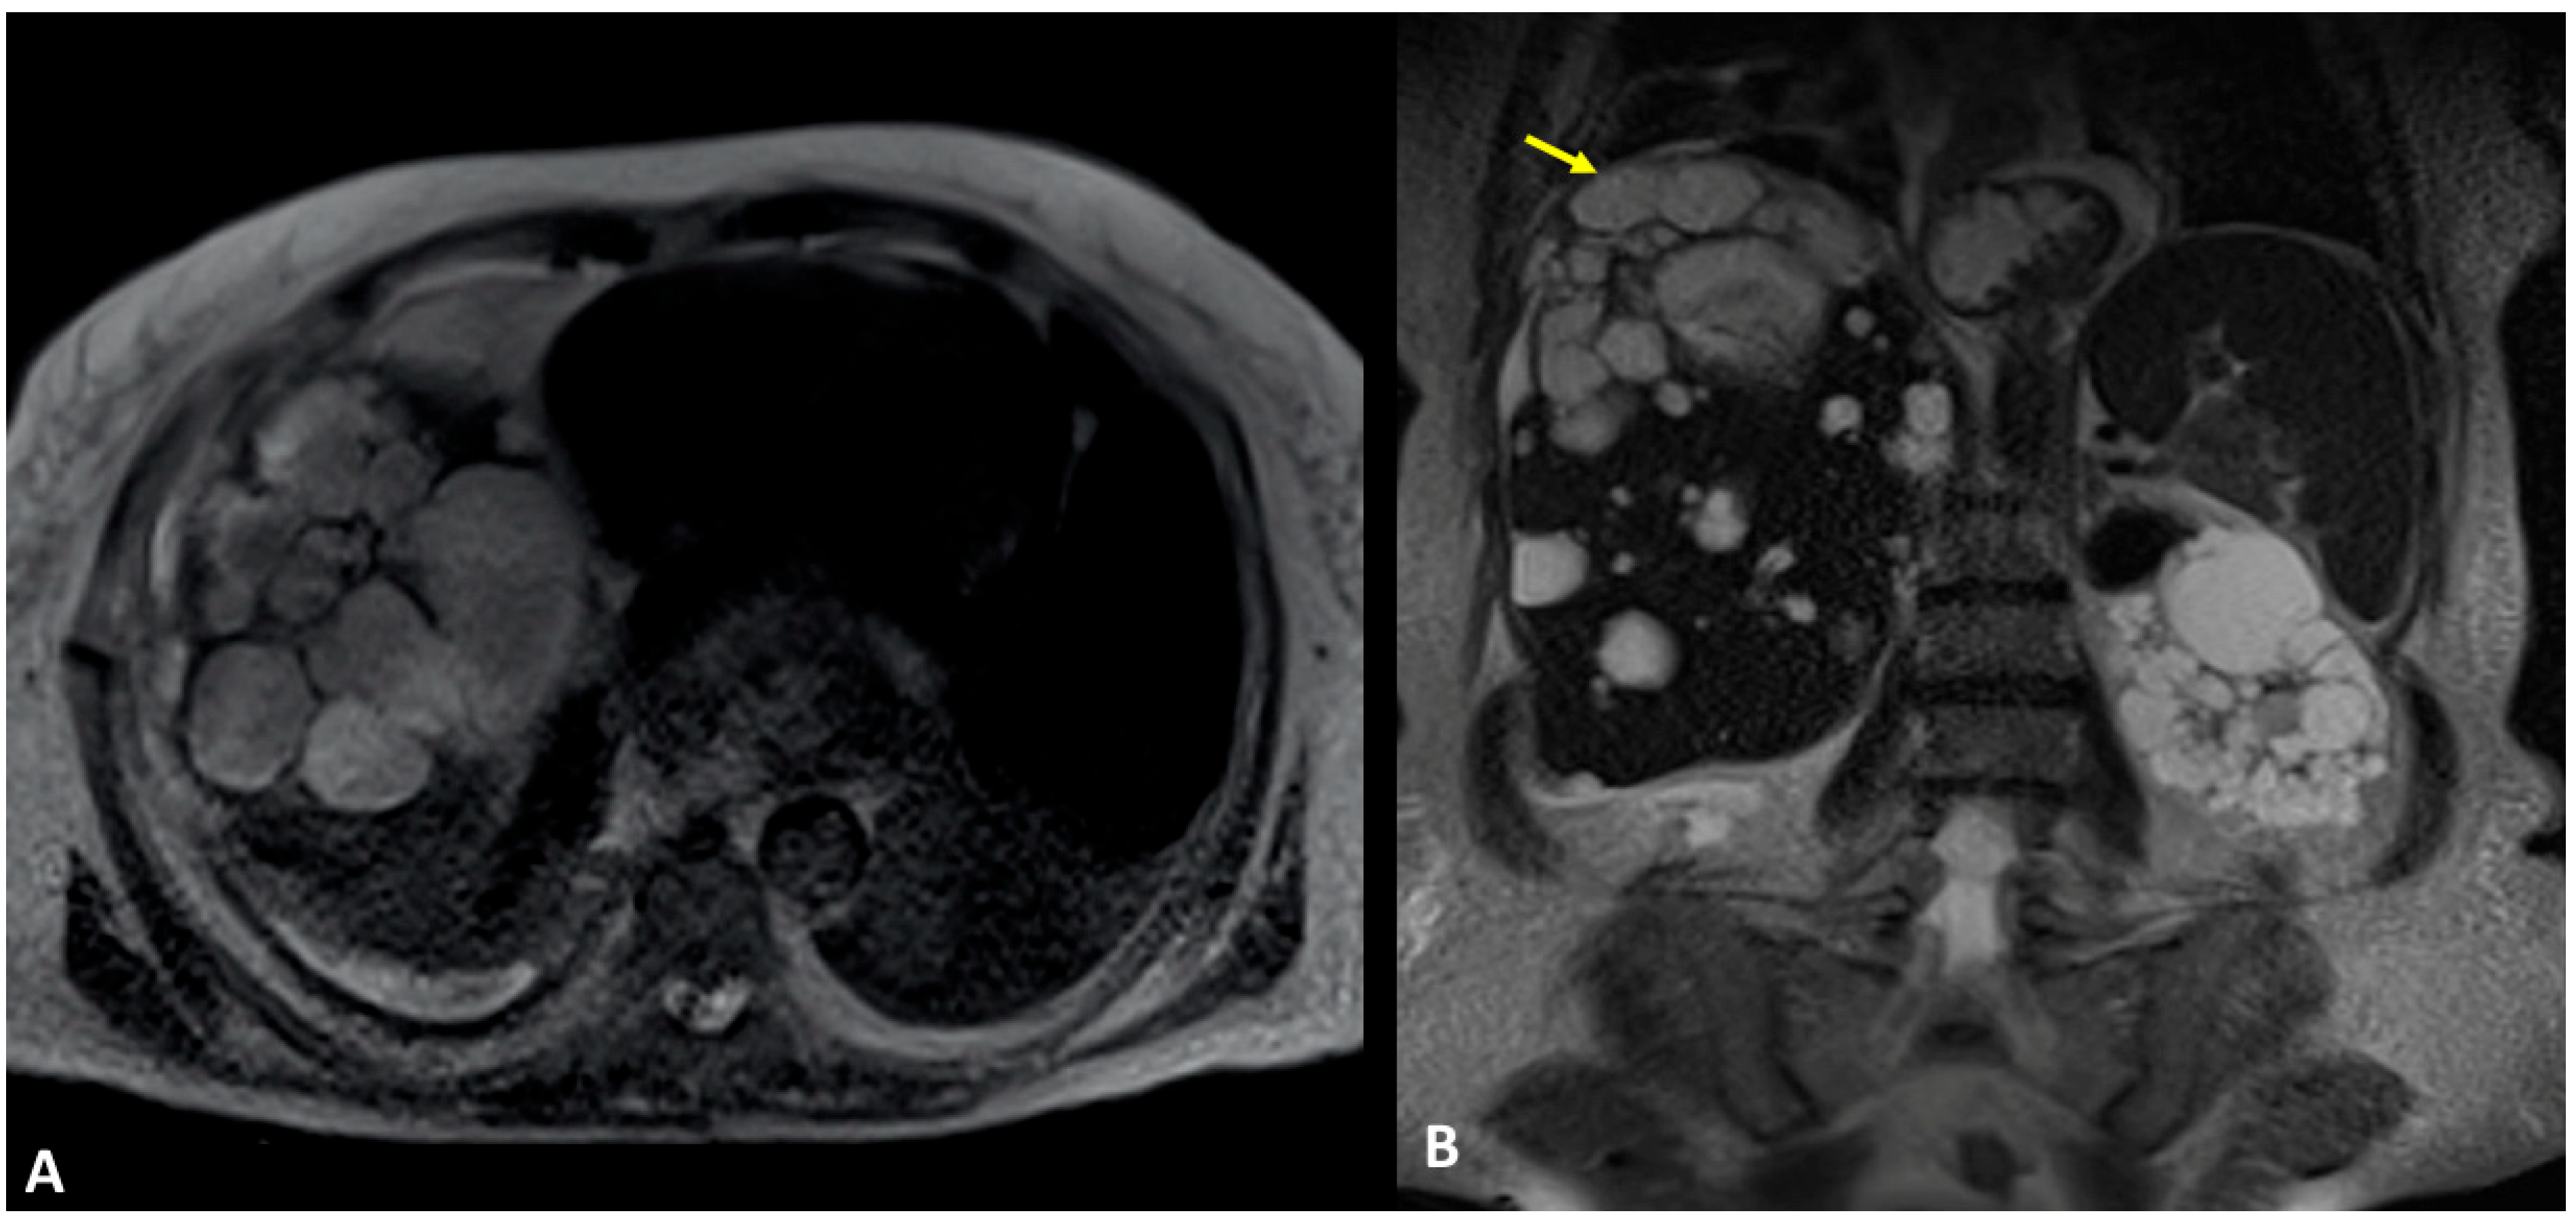

A 61-year-old woman was referred to our institution in an ER setting complaining of chest pain and dyspnea. She was affected by hepatic and renal polycystosis, she previously underwent right nephrectomy, and she had been on dialysis for the last 4 years for chronic renal failure. Physical examination revealed diminished breath sounds over the right hemithorax. Laboratory routine tests showed mild neutrophilia, increased CRP levels, and a slight increase in direct bilirubin and creatinine. She underwent a chest X-ray showing a right pneumothorax (PNX) that was drained. Consequently, the patient underwent contrast-enhanced thoracoabdominal. CT showed a right pneumothorax associated with enhanced pleural thickening. At the CT, the fluid component in the right lower lung lobe was inseparable from one of the right lobe hepatic lobe cysts (Figure 1A,B). Moreover, a focal defect was appreciable in the hepatic cyst and in the right hemidiaphragm that appeared in connection with the pleural fluid empyema. The CT findings were suggestive of HTF. The following day, MRCP was performed, which confirmed that one of the cysts, localized at the seventh hepatic segment, presented a focal wall discontinuity. MRCP further supported the hypothesis of a direct connection between the hepatic cyst and the pleural cavity, but did not identified the fistulous tract (Figure 2A,B).

Figure 2.

(A,B) Contrast-enhanced MRI, T2-weighted sequences, and axial (A) and coronal planes (B). In Figure (A), the right basal empyema and pleural thickening leaflets are confirmed. In Figure (B), the right lower lung lobe and a hepatic cyst (polycystosis) look strongly adjacent (arrow), without a definite fistulous tract.

After the placement of the naso-biliary tube, a CT scan with diluted iodinated contrast agent administered through a tube to obtain exclusive enhancement of the intrahepatic biliary tract was performed and direct communication between the biliary branch for the 7th segment and the voluminous subcapsular intrahepatic cyst with fistulization into the right pleural cavity was detected (Figure 3A,B). The final diagnosis was TBF, and specifically biliopleural fistula sustained via the direct passage of bile into a complicated liver cyst. The patient underwent surgery for atypical lower lobe lung resection at the site of the TBF, lysis of the liver adhesions with fenestration of the cysts, and closure of the fistula.